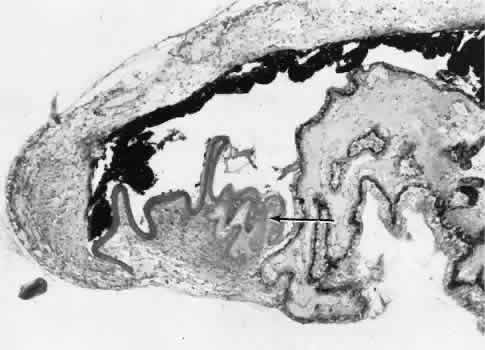

RETINAL HEALING

Wound healing of the neurosensory retina follows the principles of wound healing. There is an initial removal of all necrotic tissue by phagocytosis followed by proliferation of cells to form a chorioretinal bond. The healing, however, is modified in most instances by the lack of participation by the blood vessels.43–45 Astrocytes from the neurosensory retinaproliferate from the peripheral viable tissue into the wound and downward into the area of the subretinal space (Fig. 12). Retinal pigment epithelial cells from the peripheral viable tissue undergo fibrous metaplasia and proliferate upward into the area of the subretinal space. When the two proliferating cell types unite, a tight chorioretinal bond is formed. Increased retinal adhesiveness has been estimated to be 140% of the normal degree of adhesiveness 2 weeks after photocoagulation.46 Retinal holes may heal spontaneously if supported by an intact vitreous base or if located adjacent to the retinal pigment epithelium (Fig. 13).47,48 For the retinal pigment epithelium to differentiate, it must be in contact with overlying retinal pigment epithelium.49 Choriocapillaris repair from a photocoagulation wound of the retina appears to proceed in a manner similar to that of repair of capillary thrombosis in other tissues.50 The vascular repair process may not reproduce the lobular architecture of the native choriocapillaris.51 The choriocapillaris may regenerate in areas of restored retinal pigment epithelium.52 Proliferative vitreoretinopathy is an expression of abnormal retinal wound healing.53

Fig. 12. Light micrograph of an area over a retinal buckling element for retinal reattachment. Cryotherapy has been applied in the area, causing atrophy of the neurosensory elements of the retina. There is an intimate association of the remaining glial elements of the retina (R) with proliferated retinal pigment epithelial cells in the plane of the former subretinal space (arrow). The adhesion prevents intraretinal separation in this area. (Periodic acid-Schiff stain; × 100.)

Fig. 13. Retinal healing by proliferation of glial cells. In the presence of an intact vitreoretinal interface acting as a scaffolding, retinal glial cells are able to proliferate and seal small retinal holes. The arrow indicates artifactually detached vitreoretinal interface.